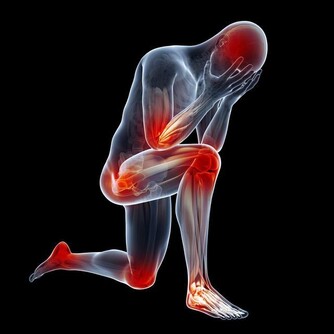

健康人精神飽滿,行為敏捷,情感合理,無暈無痛。

否則應檢查是否有心腦血管和神經骨關節系統疾病。